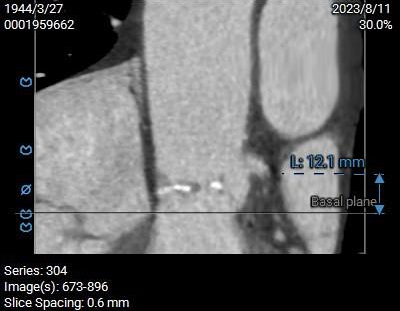

双侧冠脉开口高度可,左侧瓣叶略长,预估左侧冠脉遮挡风险较低:

双侧冠脉高度开口可,窦部较为扁平,左冠瓣叶较长,预估左冠存在一定遮挡风险,球扩及工作位密切关注冠脉血流灌注,必要时冠脉保护。